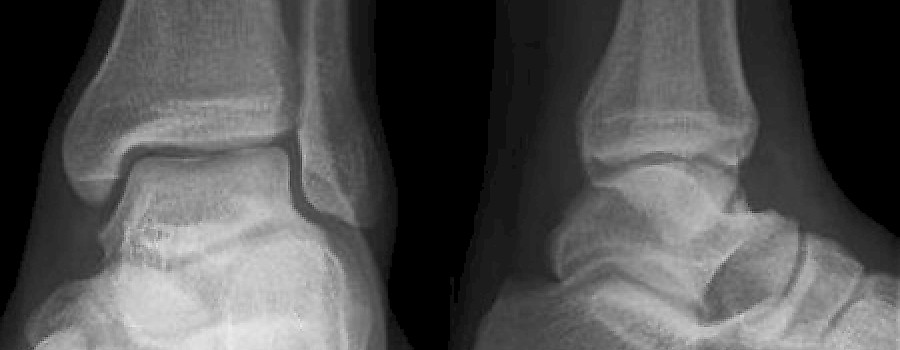

Röntgen bitte nur im Zweifelsfall

Die gehaltene Aufnahme des OSG

Sind gehaltene Aufnahmen von Sprunggelenken nach Supinationstrauma heute noch sinnvoll? Dieser Fragestellung geht Claus Becker, leitender MTRA des Uniklinikums Regensburg nach.